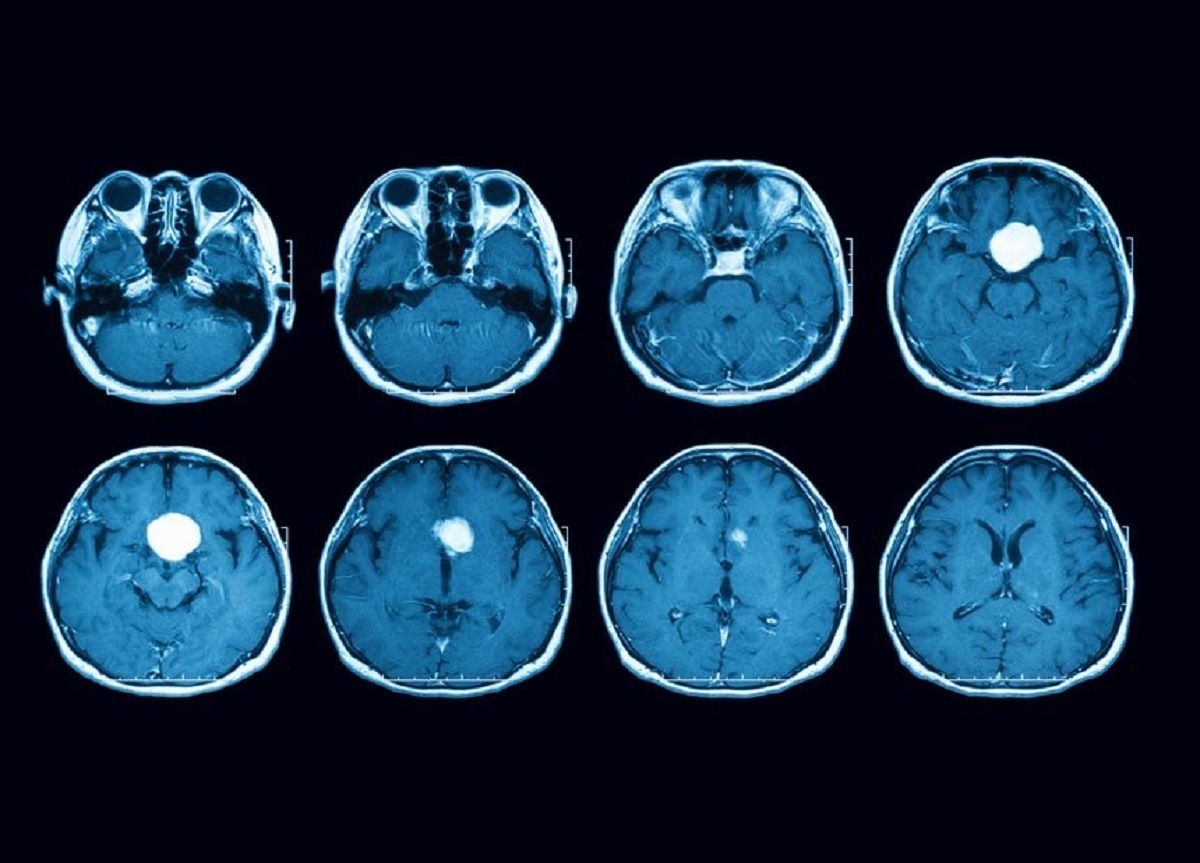

به گزارش مجله خبری نگار/عصر ایران،بیش از ۱۳۰۰ زن در سراسر ایالات متحده آمریکا علیه شرکت داروسازی فایزر (Pfizer) شکایت دسته‌جمعی مطرح کرده‌اند. این زنان ادعا می‌کنند که شرکت فایزر درباره خطر ابتلا به مننژیوم — نوعی تومور مغزی عموماً غیرسرطانی، اما بالقوه ناتوان‌کننده — در صورت استفاده طولانی‌مدت از داروی تزریقی پیشگیری از بارداری Depo-Provera هشدار کافی نداده است.

دپو-پروورا یک داروی هورمونی تزریقی است که هر سه ماه یک بار استفاده می‌شود و از اوایل دهه ۱۹۹۰ در آمریکا و استرالیا در دسترس بوده است. میلیون‌ها نفر این دارو را مصرف کرده‌اند. این دارو می‌تواند خطر ابتلا به مننژیوم (نوعی تومور مغزی معمولاً خوش‌خیم) را افزایش دهد. مننژیوم ممکن است باعث مشکلاتی مثل از دست دادن حافظه، تشنج، سردرد و مشکلات بینایی یا شنوایی شود و اغلب نیاز به جراحی دارد.